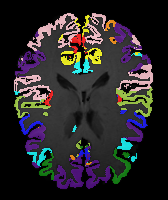

Image Manual Seg DA-1 Mono-21 DA-21 Mono-65 Refer to caption Refer to caption Refer to caption Refer to caption Refer to caption Refer to caption

Figure 2:  Examples of knee MRI registration (top) and brain MRI segmentation (bottom) results. Top: The first two columns are the moving image/segmentation and the target image/segmentation followed by the warped moving images (with deformation grids)/segmentations by different models. Bottom left to right: original image, manual segmentation, and predictions of various models. Mono-i𝑖i and DA-i𝑖i represent the mono- and DA models with i𝑖i manual segmentations respectively.

Results: All trained networks are evaluated using Dice overlap scores between predictions and the manual segmentations for the segmentation network, or between the warped moving segmentations and the target segmentations for the registration network. Tabs. 1 and 2 show results for the knee and brain MRI experiments respectively in Dice scores (%). Fig. 2 shows examples of knee MRI registrations and brain MRI segmentations.

Brain results: Dice scores for segmentation and registration increase by about 2.6 and 3.5 respectively for the cortical structures of the brain MRIs.

Qualitative results: DA achieves more anatomically consistent registrations than the mono-networks on the knee (Fig. 2) and Brain MRI samples (see supplementary material).

Moving Target Mono-0 Mono-21 DA-1 DA-21 Mono-65 Refer to caption Refer to caption Refer to caption Refer to caption Refer to caption Refer to caption Refer to caption Refer to caption Refer to caption Refer to caption Refer to caption Refer to caption Refer to caption Refer to caption